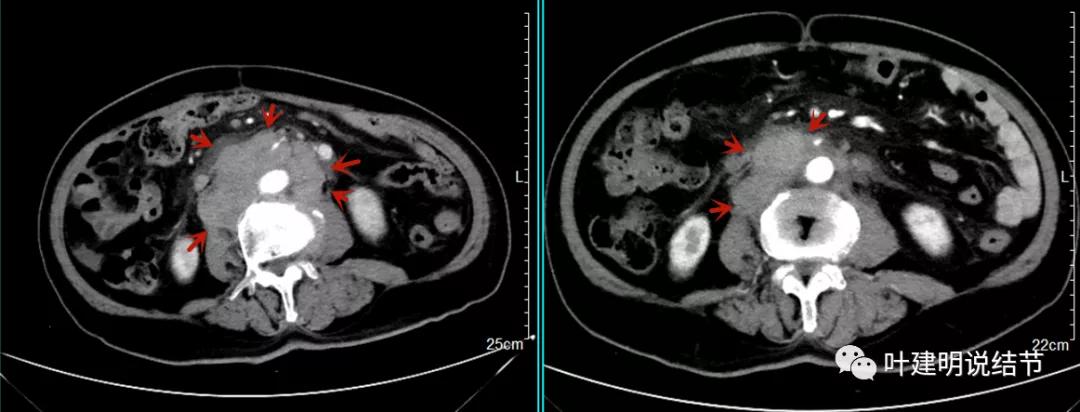

上图同样左侧是治疗前的,右侧经过2周期免疫加化疗后复查的,可见病灶缩小甚至超过9成。下面是治疗前与后来于6月底复查的:

可见经过4个多月的治疗,转移灶已经几乎看不出来了!目前患者无任何不适,正常进食,也无腹部症状或体征,仍在持续特瑞普利单抗维持治疗中。我们期待其更长久的获益与持久的疗效,为其他晚期食管癌积累自己的实战经验(开会或文献上别人的介绍没有自己遇到的如此直观,也没有如此深的印象。所以我一直觉得临床经验,尤其自己亲身经历积累的经验才更有说服力,也更有感受)。